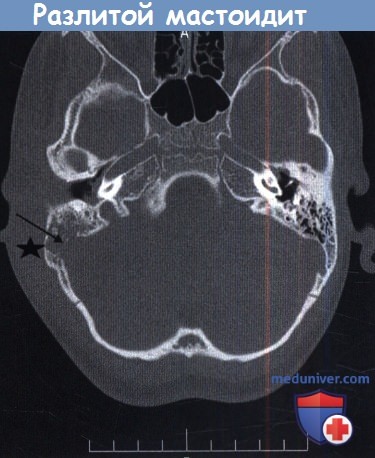

Все осложнения острого среднего отита — воспаления ухаКак писал Shambaugh в предисловии к книге «Хирургия уха», «ни одна отрасль медицинской науки не была изменена на более глубоком уровне, не продвинулась быстрее и не получила столько пользы от сульфаниламидов и антибиотикотерапии, как хирургия уха». Авторы вспоминают рассказы очевидцев о том, как после введения антибиотиков в Чикаго чудесным образом освобождались инфекционные больницы; это изменения нашло отражение и в отологии. В настоящее время проблема более коварна. Для молодого отиатра неприятным сюрпризом станут последствия вирусного поражения организма, когда у пациента с отитом в течение 12 часов развивается коматозное и почти предсмертное состояние. При написании данной главы авторы ставили задачу каталогизации и обобщения современных представлений о местных и внутричерепных осложнениях среднего отита в надежде, что катастрофические осложнения могут быть предотвращены при своевременном вмешательстве. Средний отит — это воспаление части или всего мукопериоста слуховой трубы, барабанной полости, антрума и всех пневматизированных пространств височной кости. Осложнения среднего отита определяются как распространение инфекции за пределы среднего уха. Как хронический, так и острый средний отит могут вызывать осложнения. До применения антибиотиков 52% осложнений были связаны с вирулентным острым средним отитом. В настоящее время наиболее частые осложнения возникают на фоне хронического среднего отита. Заболеваемость и смертность от осложнений можно минимизировать если хорошо знать специфические виды дренажа уха, основу патологического процесса, ранние проявления и симптомы осложнений. Эти обобщения важны в настоящее время, так как редкость возникновения осложнений ограничивает личный опыт многих отиатров. а) Перфорация pars tensa барабанной перепонки как осложнение острого воспаления уха. Острый средний отит бактериальной природы обычно поражает детей дошкольного возраста, как правило, источником инфекции является носоглотка. Первоначально воспаление в среднем ухе протекает с нагноением, осложнениями и их разрешением. За экссудацией серозно-фиброзного содержимого в среднем ухе следует воспалительная стадия, гиперемия и отек слизистой оболочки. При нарастании объема жидкости в среднем ухе давление на барабанную перепонку увеличивается, и если не выполнена миринготомия, происходит перфорация барабанной перепонки, обычно в передне-нижнем квадранте. Боль стихает, интоксикация и лихорадка уменьшаются. В большинстве случаев после стихания воспаления перфорация спонтанно закрывается. В европеоидной популяции перфорация персистирует у 2% пациентов. Снижение слуха ассоциировано с перфорацией и обычно умеренное. Пробы Вебера и Ринне положительные с обеих сторон. Аудиометрические исследования подтверждают камертональные тесты. Причины кондуктивной тугоухости при перфорации барабанной перепонки рассмотрены в отдельной статье на сайте. Перфорация барабанной перепонки может быть закрыта хирургическим методом. Каковы шансы на успех мирингопластики в таких случаях? Дисфункция слуховой трубы уменьшает шансы успешной мирингопластики. К сожалению, точная предоперационная оценка слуховой трубы невозможна. Состояние противоположной слуховой трубы не является определяющим. Лучшая корреляция определяется между дисфункцией слуховой трубы и пневматизацией сосцевидного отростка. Результат эффективности мирингопластики тем выше, чем лучше пневматизация сосцевидного отростка, достигая 95%. б) Острый мастоидит/субпериостальный абсцесс как осложнение острого среднего отита. Острый мастоидит представляет собой распространение воспаления острого среднего отита на антрум и клетки сосцевидного отростка. Такое распространение возможно через вход в пещеру, соединяющий эпитимпанум с антрумом. По данным Nager, «легкое течение острого мастоидита всегда сопровождает острый средний отит, однако воспалительный процесс локализуется в надкостнице». Таким образом, любое воспаление барабанной полости лучше называть тимпаномастоидит. Обычные КТ и МРТ исследования выявляют «мастоидит» даже при отсутствии клинических данных, боли и болезненности над сосцевидным отростком или любого доказательства разрушения костных ячеек. В таких случаях несоответствия необходимо проследить развитие тимпатномастоидита в субпериостальный абсцесс: если во время тимпаномастоидита вход блокирован воспалительной тканью, слизисто-гнойное содержимое может скапливаться в антруме и смежных ячейках. При усугублении инфекционного процесса, продолжающемся блоке входа в пещеру и неадекватной антибактериальной терапии может возникнуть ретроградный тромбофлебит с отеком и целлюлитом мягких тканей заушной области, вызывая ипсила-теральную боль в заушной области, отек и индурацию. Если гнойный процесс не дренируется спонтанным или хирургическим путем, происходит разрушение костных стенок клеток сосцевидного отростка, что приводит к сливному мастоидиту. Начиная с этой стадии, прогрессирование идет непрерывно с возможностью следующих осложнений: • Эрозия кортикального слоя с формированием субпериостального абсцесса • Медиальное распространение на пирамиду с вовлечением верхушки, классическими симптомами и синдромом Градениго • Переднее распространение, патологический процесс распространяется на лабиринт или канал лицевого нерва, в результате чего возникает паралич лицевого нерва и /или головокружение с или без сенсоневральной тугоухости • Распространение к верхушке сосцевидного отростка с формированием абсцесса Бецольда • Распространение за крышу барабанной полости или угол Траутманна, что может привести к развитию эпидурального абсцесса • Проникновение в перилимфу или цереброспинальную жидкость приводит к менингиту. Аксиальный срез височной кости, разлитой мастоидит. Отек латеральнее сосцевидного отростка. В многоцентровом исследовании 223 случаев мастоидита/острого среднего отита, Luntz et al. выявили, что в 88% случаев мастоидит возник у детей в возрасте до восьми лет. При поступлении в стационар в 22% случаях имелись местные или интракраниальные осложнения. Наиболее часто выявляли изолированную флору: Streptococcus pneumoniae, Streptococcus puogenes, Staphylococcus aureus, Staphylococcus (коагулазонегативный), Haemophilus influenzae, Pseudomonas aeruginosa. Культуры Pseudomonas spp. выявлены у 18 пациентов (8%), но следует отметить, что у 50% из них образец материала был взят из наружного слухового прохода. У 12 из 18 пациентов излечение произошло без осложнений, хотя противосинегнойные антибиотики не использовались. Эти авторы также обнаружили, что лечение антибактериальными каплями при остром среднем отите не гарантирует отсутствие мастоидита. Ранняя миринготомия позволяет обеспечить менее осложненное течение мастоидита. Несливной мастоидит эффективно лечат, используя внутривенное введение специфических антибиотиков, миринготомию и установление вентиляционной трубки (шунта). Однако в 20% случаев такого лечения недостаточно, и необходимо выполнить кортикальную мастоидэктомию. Внимательное наблюдение за такими детьми, позволяет предотвратить развитие серьезных осложнений. Разлитой мастоидит и субпериостальный абсцесс требуют детальной оценки и выполнения рентгенологического обследования. Лечение включает антибактериальную терапию препаратами четвертого поколения, миринготомию и кортикальную мастоидэктомию. Важно помнить, что у младенцев и маленьких детей шилососцевидное отверстие располагается на латеральной поверхности сосцевидного отростка. Следовательно, заушный разрез должен быть модифицирован и не должен спускаться ниже дна наружного слухового прохода с мониторингом лицевого нерва. Иммунокомпрометированные пациенты более восприимчивы к развитию разлитого мастоидита. Пациент на рисунке ниже был ВИЧ-позитивным. После эпизода острого среднего отита развился зигоматицит. При неадекватном лечении острого среднего отита могут возникнуть осложнения. Подострое течение среднего отита, следствие неадекватной терапии, замедляет стихание первичных симптомов острого отита, с прогрессированием заболевания и формированием острого мастоидального абсцесса без типичной интоксикации. Holt и Gates описали опыт лечения девяти пациентов с так называемым маскированным мастоидитом, у которых возникли интратемпоральные и/или внутричерепные осложнения. История заболевания в таких случаях представляет персистируютцее слабое раздражение, диарею и пульсацию в ухе после кажущегося улучшения острого отита после применения антибактериальных препаратов. Вялотекущее воспаление было обнаружено Meyerhoff et al. в височных костях при остром среднем отите. Основываясь на клинических данных, авторы заключили, что анаэробная флора, такая как Peptococcus spp. и Bacteriodes spp., развиваются в анаэробной среде сосцевидного отростка при блоке входа в пещеру грануляционной тканью. Эти анаэробные микроорганизмы обладают высокой вирулентностью и приводят к развитию остеита с минимальной или отсутствующей болью. У пациента на рисунке ниже выявлен безболезненный отек заушной области. Как часто бывает в таких случаях, барабанная перепонка утолщена, но интактна. При КТ выявлен субпериостальный абсцесс, потребовавший хирургического дренирования и кортикальной мастоидэктомии. В девяти случаях маскированного мастоидита Holt и Gates обнаружили ассоциированные осложнения, включавшие эпидуральный абсцесс (2 случая), паралич лицевого нерва (1), менингит и эпидуральный абсцесс (1), менингит (2), абсцесс мозга (2), и энцефалит (1). Важно очень внимательно следить за этим коварным заболеванием и при возможности выполнять КТ височной кости для исключения осложнений. При остром осложнении среднего отита необходимо выполнить КТ с контрастированием для выявления тромбофлебита или внутричерепных осложнений. Фотография латеральной поверхности височной кости доношенного новорожденного. Сосцевидный отросток еще не развит и шилососцевидное отверстие расположено высоко на латеральной поверхности височной кости (стрелка). Клиническая фотография ВИЧ-позитивного пациента с абсцессом скулового отростка. Клиническая фотография ребенка с правосторонним стертым мастоидитом. Стрелкой указано оттопыривание ушной раковины. Аксиальная проекция КТ височных костей. в) Петрозит как осложнение острого среднего отита. Петрозит (известный как апицит) — воспаление пневматизированных ячеек каменистой порции височной кости и редкое осложнение острого среднего отита. У многих людей верхушка пирамиды височной кости мало пневматизирована, при этом выделяют два основных вида пневматизации: 1. Задняя группа клеток, которые продолжаются в антрум и эпитимпанум, группируясь вокруг полукружных каналов в основании пирамиды, и располагаются медиальнее верхушки каменистой кости. 2. Передняя группа клеток, которая расходится от мезотимпанума, гипотимпанума и протимпанума и расположена вокруг улитки ближе к верхушке каменистой кости. Schuknecht классифицировал петрозит на острый и хронический. Острый петрозит: С точки зрения патологии острый петрозит аналогичен острому тимпаномастоидиту, описанному ранее. В большинстве случаев воспаление разрешается самостоятельно, бессимптомно. Если продукты воспаления сохраняются, то может возникнуть остеит в верхушке пирамиды височной кости, что приводит к диплопии и ретро-орбитальной боли. Компрессия отводящего нерва в канале Дорелло под связкой Грубера (каменисто-клиновидной), вызывает паралич ипсилатеральной латеральной прямой мышцы. Ипсилатеральный тройничный нерв, расположенный на верхушке пирамиды, также воспаляется, что приводит к ретро-орбитальным болям. Триада симптомов: средний отит, ипсилатерельная ретро-орбитальная боль, парез отводящего нерва известна как синдром Градениго. Диагноз подтверждается КТ-исследованием височной кости с высоким разрешением. Хронический пертозит: В дополнение к воспалительным изменениям происходит формирование новой костной ткани и резорбция. Остеит, затрагивающий костный лабиринт, твердую мозговую оболочку или вены, может вызывать лабиринтит, менингит, эпидуральный абсцесс или абсцессы мозга. Лечение петрозита включает системную антибактериальную терапию и хирургический дренаж. Первый этап включает выполнение мастоидэктомии с обнажением полукружных каналов. В этом случае можно подойти к верхушке несколькими доступами в зависимости от расположения инфекционного процесса, пневматизации височной кости и слуха. При глухом ухе транслабиринтный и чрезуш-ный доступы являются наиболее простыми и обеспечивают хороший обзор верхушки. Данный доступ возможен и при сохранившемся слухе, когда клиническое состояние угрожает жизни пациента, так как этот подход считается более удобным и безопасным, однако приведет к потере слуха. При переднем расположении более оптимальным считается трансулитковый доступ. При слышащем ухе подвисочный и подулитковый доступы обеспечивают подход к переднему расположению патологического очага. Ретролабиринтные или субаркуатные доступы позволяют выполнить дренаж задних клеток с сохранением слуха. г) Паралич лицевого нерва как осложнение острого воспаления уха. У детей чаще возникает вторичный паралич лицевого нерва после перенесенного острого среднего отита. Как и при других осложнениях острого среднего отита, риск развития снижает назначение антибиотиков. Обычно первые симптомы паралича возникают спустя несколько дней после начала острого среднего отита. Паралич лицевого нерва редко возникает как начальный симптом острого среднего отита. Патофизиология: Пути распространения патологического процесса: 1. Через естественные дегисценции в фаллопиевом канале, часто в барабанном отделе. 2. Через естественные анатомические образования, соединяющие среднее ухо и просвет фаллопиева канала, такие как, канал стременной мышцы, сосудисто-нервные пучки, воздухоносные клетки сосцевидного отростка, прилежащие к фаллопиеву каналу. 3. Через прямой переход воспаления на фаллопиев канал при локализованном остеите. Микроорганизмы, вызывающие паралич лицевого нерва, схожи с таковым при остром среднем отите. Гнойный процесс или остеит вокруг обнажившегося нерва приводит к воспалению и отеку нерва. Токсины и ишемия играют второстепенную роль. Лечение: 1. Лечение предшествующего отита соответствующими антибиотиками минимум 10 дней. В тоже время могут положительно повлиять миринготимия, а при необходимости и шунтирование барабанной полости. Пациента на рисунке 26-6 лечили консервативно, и, как видно, результат был удовлетворительным. 2. Мастоидэктомия выполняется в случае отсутствия ответа на консервативную терапию. Декомпрессия лицевого нерва не обязательна, так как во многих случаях, полное выздоровление отмечается в >95% случаев вторичного паралича лицевого нерва после острого среднего отита. а — Клиническая фотография пациентки с параличом лицевого нерва. б — Та же пациентка после двухнедельного курса лечения острого среднего отита. д) Лабиринтит как осложнение острого воспаления уха. По классификации Schuknecht выделяют три типа лабиринтита: 1. Серозный лабиринтит 2. Отогенный гнойный лабиринтит 3. Менингеальный гнойный лабиринтит Серозный лабиринтит является осложнением острого или хронического среднего отита. Предполагается, что экзотоксины бактерий проникают во внутреннее ухо через овальное или круглое окно или фистулу лабиринта. Как осложнение острого среднего отита наиболее вероятны первые два пути распространения инфекции. Согласно Schuknecht, в острой фазе нет клинических признаков для дифференци-ровки серозного и гнойного лабиринтита. Диагноз ретроспективный. Если вестибулярные и слуховые функции частично или полностью восстанавливаются, можно сделать вывод о том, что лабиринтит был серозным. Margolis et al. исследовали слух на высоких частотах у детей, перенесших острый средний отит в контрольной группе. Было обнаружено, что в группе детей, перенесших острый средний отит, снижение слуха на высоких частотах встречалось чаще. В дополнение к антибактериальной терапии среднего отита при выявлении или подозрении на лабиринтит следует назначать адьювантную терапию глюкортикостероидами. — Также рекомендуем «Все осложнения хронического среднего отита — хронического воспаления уха» Оглавление темы «Осложнения среднего отита.»: